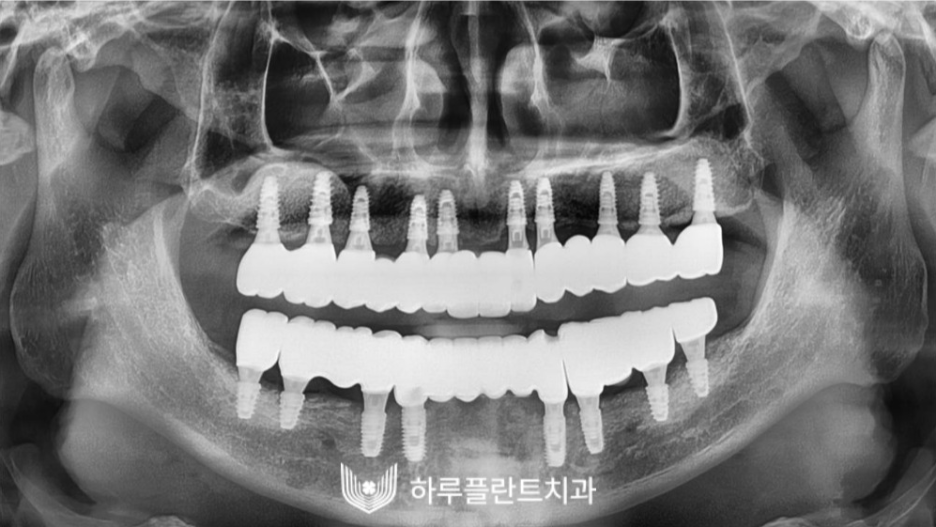

2022.12

많은 양의 고난도 뼈이식이

필요한 상황이었는데요,

잇몸 상태에 맞는 적절한 양의

골 이식재를 사용해 뼈이식 후

임플란트를 완성한 엑스레이 사진입니다.